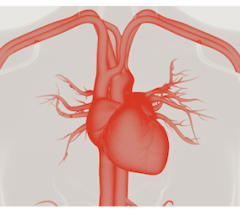

Cardiac PET/CT represents a major advancement in cardiovascular diagnostics, offering significant clinical and ...

Cardiac positron emission tomography (PET) is growing in popularity among cardiologists because it provides the ability ...